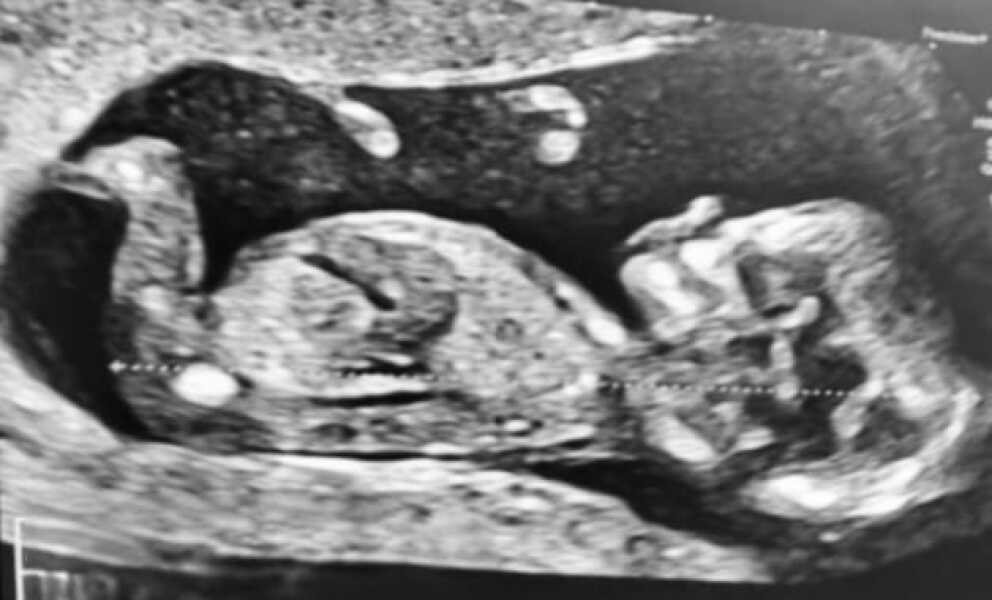

Just had our scan, @TTCRainbow was right, she's a little girl!

TTCRainbow · 23/05/2023 19:05

@DiamondApricot omg 🥺🥺😭😭🩷🩷 she is perfect!

Myperfectchaos · 24/05/2023 08:53

@DiamondApricot aww how cute!! I. Have my gender scan on Sunday

Sb86 · 24/05/2023 08:55

Awwwww beautiful 🥰 @DiamondApricot